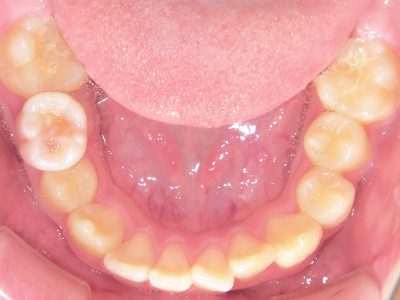

ないき歯科クリニックでは、上あごの成長不足を補い、鼻呼吸を獲得しつつ歯列を整え、将来のお口をより健康な状態にすることをゴールに定める矯正治療をおこなっています。

矯正装置を装着し、調整しながら少しずつ歯を移動させ、歯並びを整えていきます。

状態によって家庭でのトレーニングが必要な場合もあり、治療期間も個人差があります。

あくまでも平均値ではありますが、一般的には月1回程度来院頂き、1~2年程度を目安に治療を進めていきます。